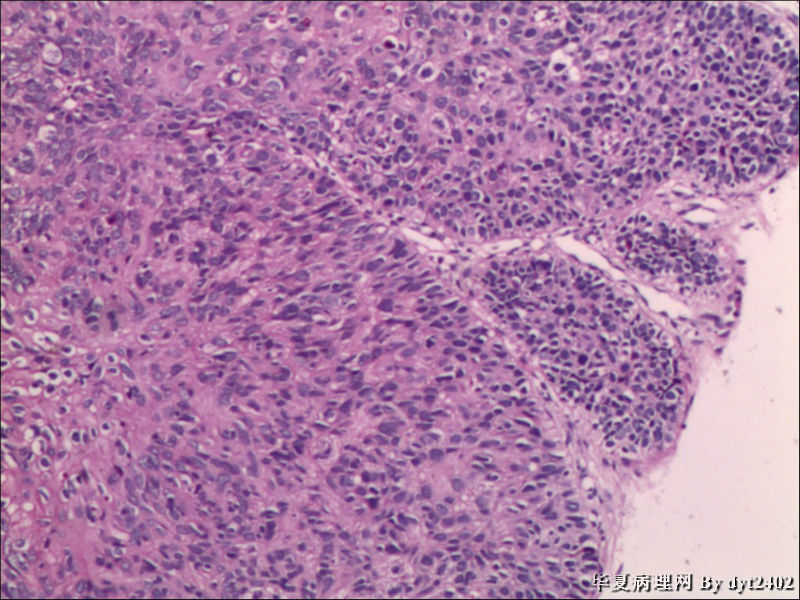

• 宫颈活检 其中一点较迷糊图1

图1

四点中三点是CIN iii,另一点怀疑有更重病变

这个病人是44岁,去年11月底阴道脱落细胞、TCT均见细胞异常,建议活检,病人犹豫,接着单位组织到外院体检时做阴道镜正常,后霉菌感染,此时宫颈未涂醋肉眼看还光滑,直至今年3月来做活检,事前做白带检查又见异常细胞,宫颈未涂醋见后上唇白上皮,涂醋酸后上下唇都有厚白上皮,镶嵌,夹活时上皮剥脱,未能夹到间质,阴道镜医生说至少有CIN III 到原位癌了。。镜下其中3点CIN III无疑,唯有9点处如6、7、11、14等所示结构,但我未见间质浸润,不能说是浸润癌,不知道有没基底细胞样鳞癌的可能,我发了个原位癌不除外深部有更重病变,。